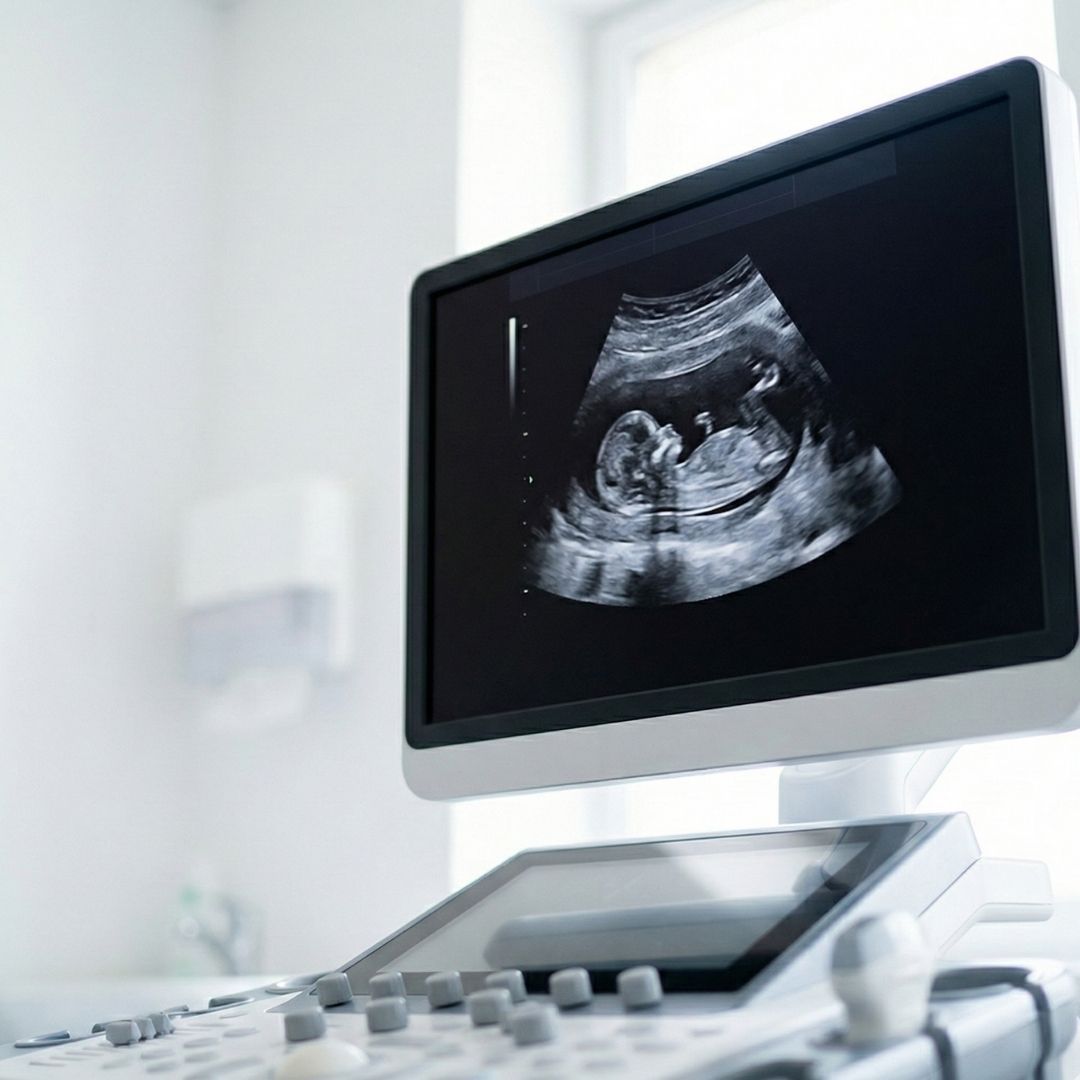

Comprehensive Obstetrics and Midwifery Care

Our team offers a unique collaborative experience that blends the expertise of physicians with the personalized touch of nurse midwives. We provide complete pregnancy care from preconception counseling to labor and delivery at Lakewood Ranch Medical Center. We advocate for low-intervention, natural labor whenever possible, ensuring your birth experience is as memorable and empowering as you envisioned it.